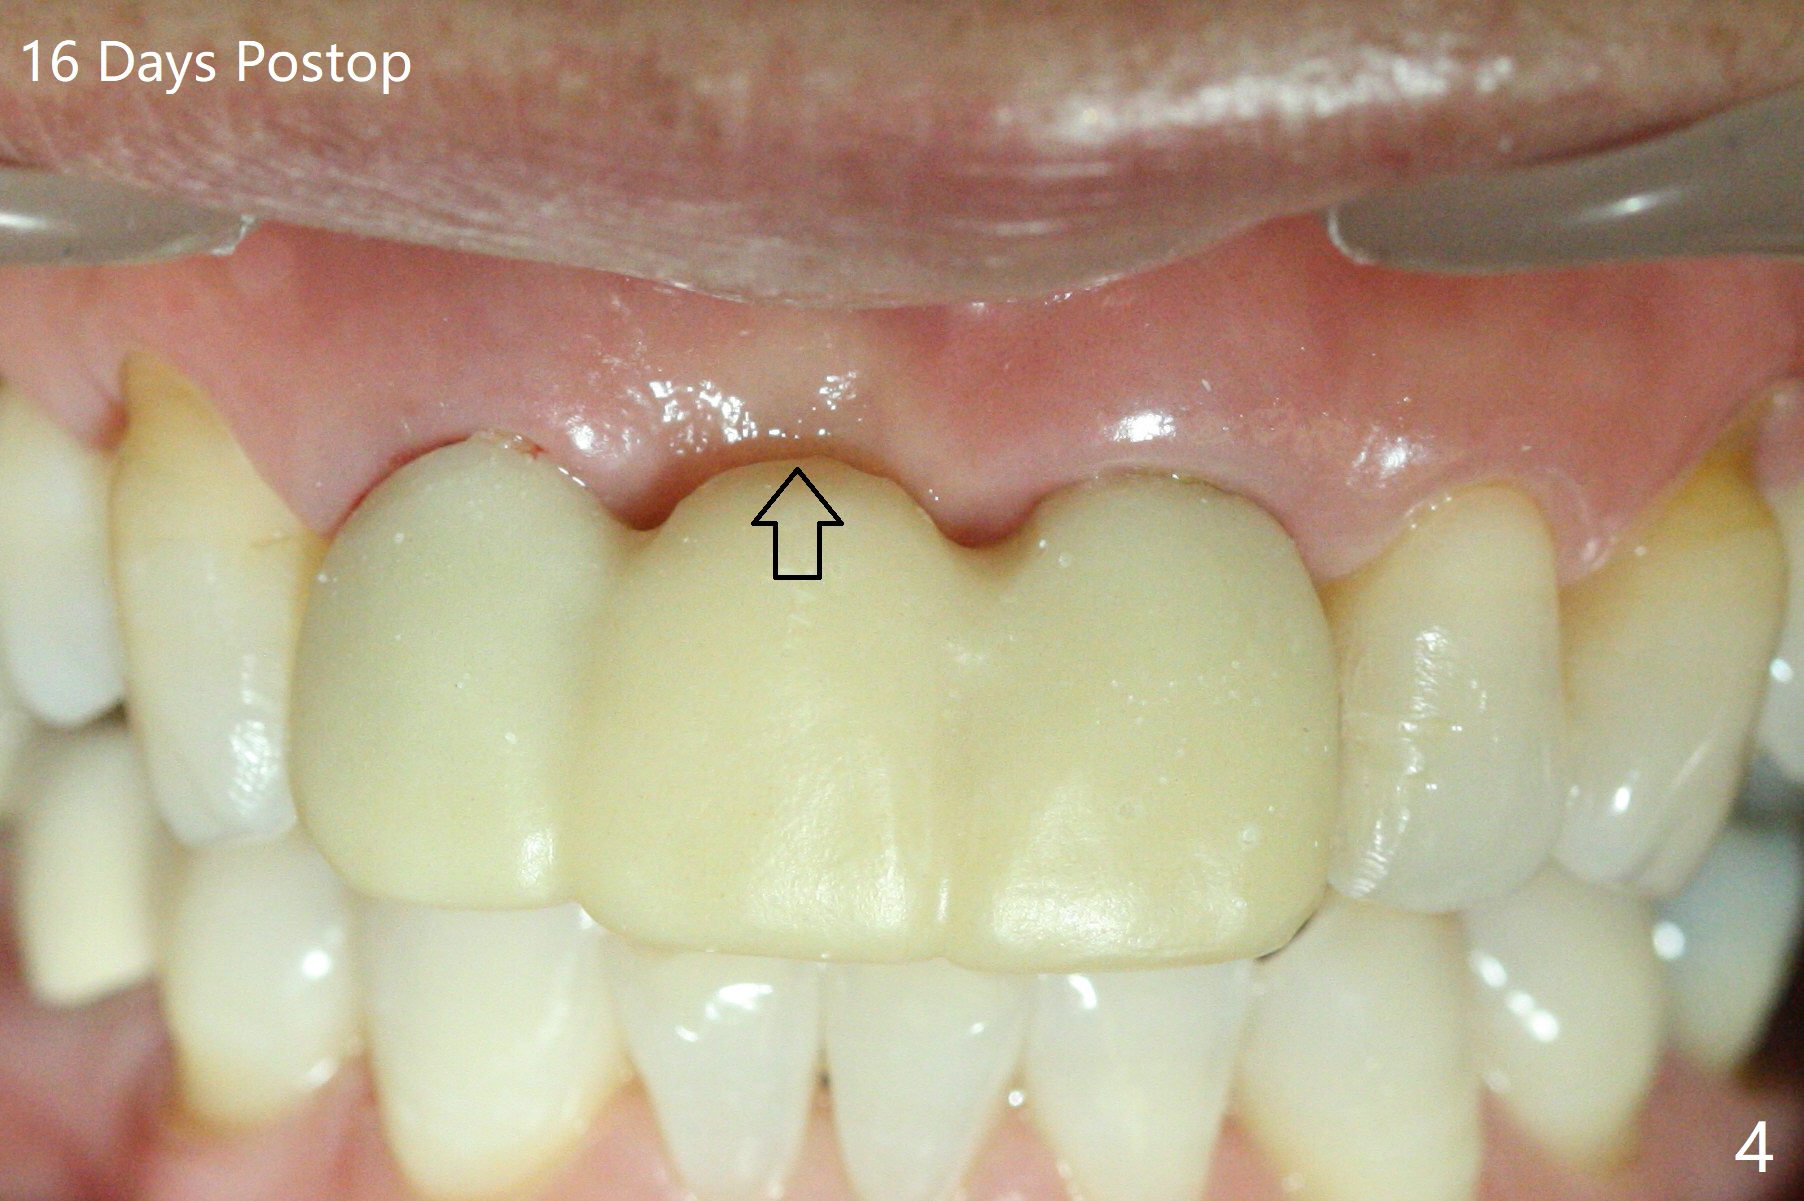

Since the pontic (Fig.1 #8) of the existing failed FPD has severe buccal concavity (*), socket shield is performed when #7 and 9 are extracted (Fig.2,3 *). Angled abutments are placed when 3.5x13 mm implants are inserted with guide. An immediate provisional FPD is fabricated. Acrylic is added to the pontic of the temporary FPD (Fig.4 arrow) to form a concave pontic gingiva (blanch)16 days postop. The patient returns 3.5 m postop with concern over temp being bulky and turning yellow. With Cetacaine and 1-0 cord, labial reducion is done for 7,9 abutments as well as 7 incisal reduction. The provisional is relined to increase 7 8 crown length. Next visit we will continue modification of temporary. Photos will be taken before and after modification (buccal and incisal views). The patient complains of occasional pain at #7. Check whether the socket shield at #7 is a culprit. In fact the implant at #7 is normal. Manipulation of the provisional does not help cosmetics much. A permanent restoration is delivered 5.5 months postop (Fig.7-9).